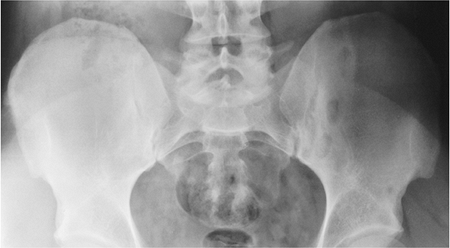

FIGURE 13-6 Reiter involvement of the sacroiliac joint. Involvement is bilateral but asymmetric.